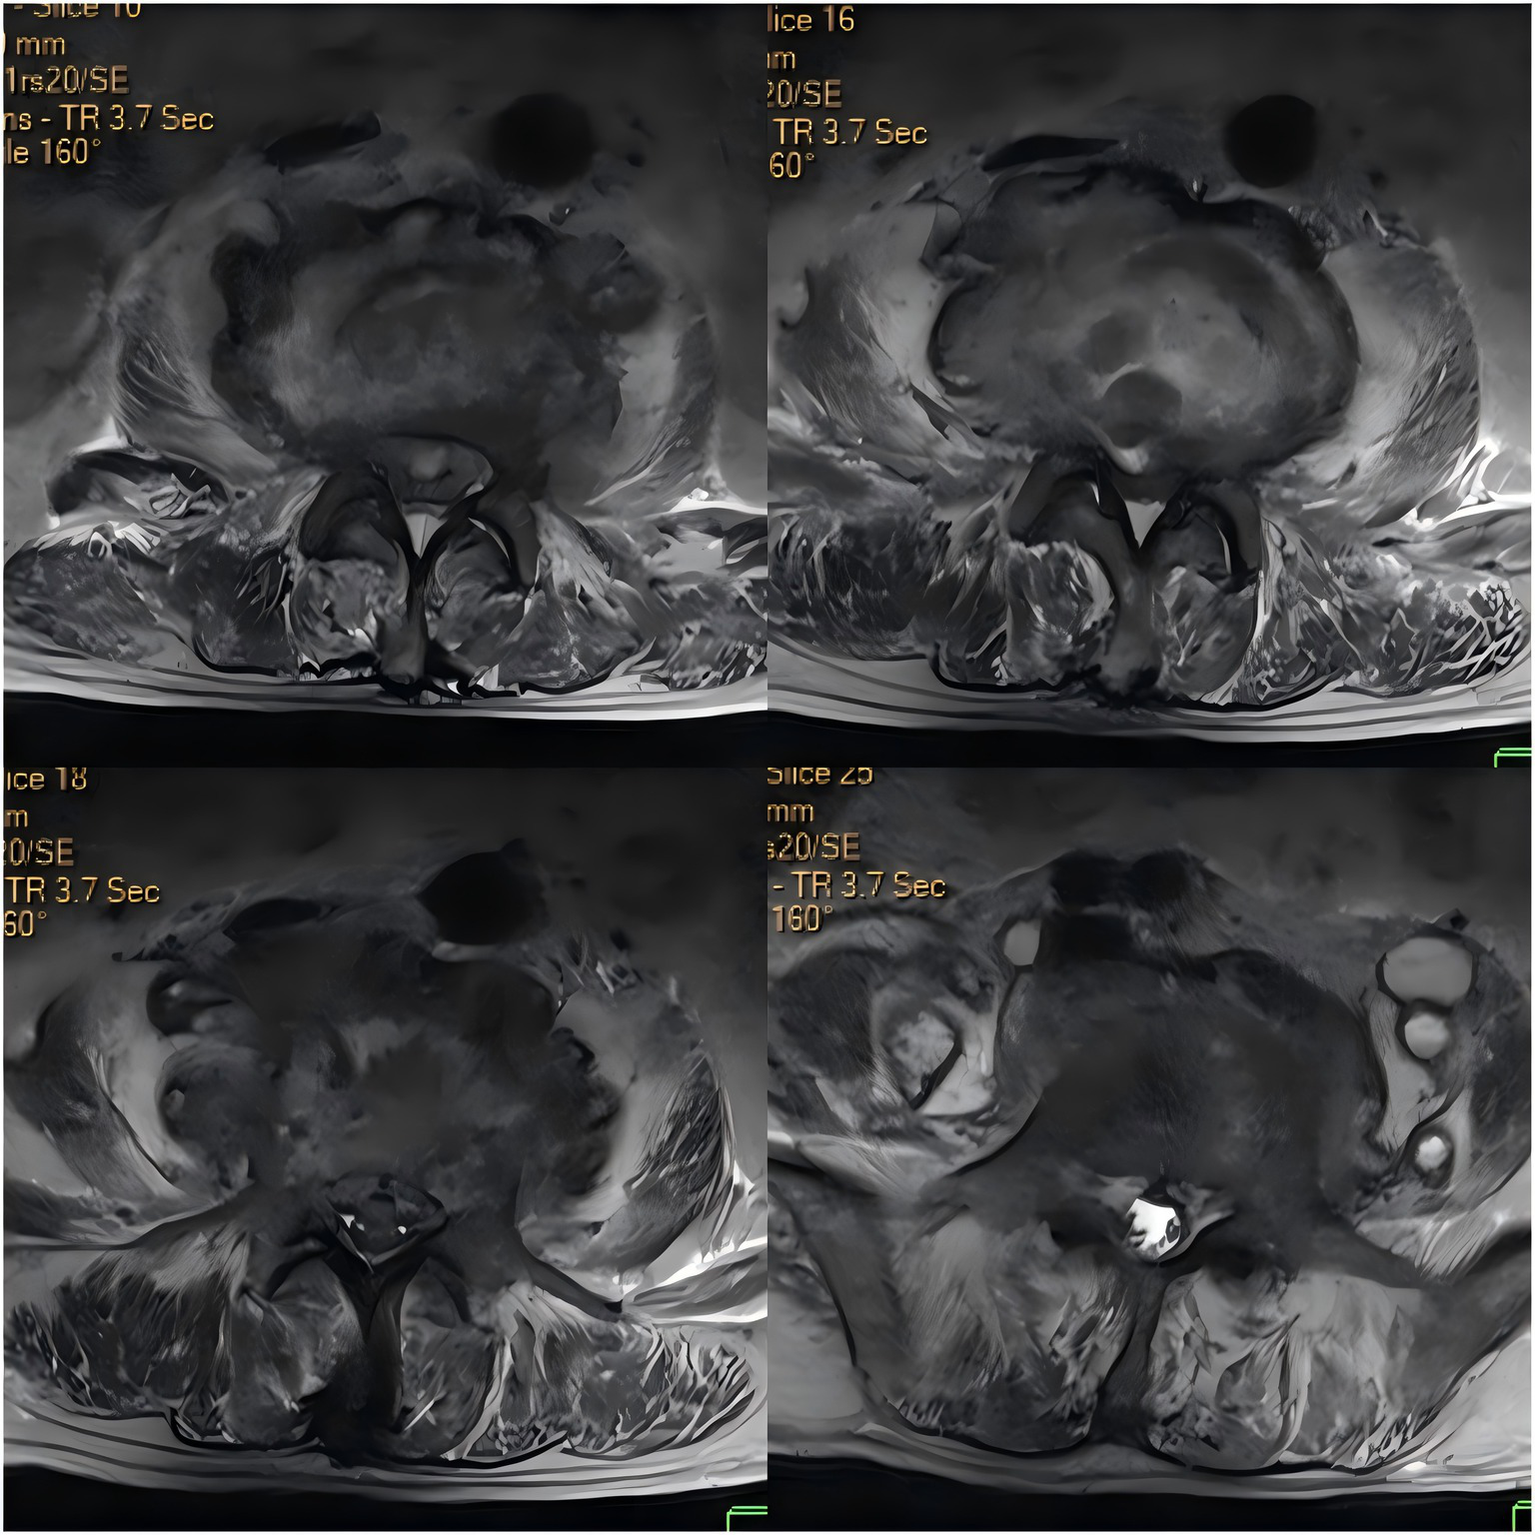

Upon admission, the patient’s body temperature was 40.3 °C, accompanied by chills, fatigue, shortness of breath, and tachycardia, but his blood pressure was normal (126/88 mmHg). Laboratory tests showed a white blood cell count of 8.8 × 109/L (normal range: 3.5–9.5 × 109/L), neutrophil count of 83.10 × 109/L (normal range: 1.8–6.3 × 109/L), lymphocyte count of 11.40 × 109/L (normal range: 1.1–3.2 × 109/L), procalcitonin level of 1.175 ng/mL (normal range: <0.05 ng/mL), interleukin-6 level of 84.46 pg/mL (normal range: <7 pg/mL), erythrocyte sedimentation rate (ESR) of 58 mm/h (normal range: 0–15 mm/h), negative tuberculosis PCR, a negative interferon-gamma release assay (IGRA), negative tuberculosis PCR, negative Brucella agglutination test, negative TORCH test results, and multiple negative blood and sputum cultures. Persistently negative conventional cultures in CREC infections are not uncommon, as these pathogens often require specialized media or prolonged incubation for detection (10). CT scans revealed irregular bone structures in the L2–L5 intervertebral discs, with fluid-filled dark areas around the discs and bilateral psoas muscles, suggesting tuberculous abscess changes. Lumbar MRI showed tuberculosis in the L2–L5 vertebrae, with surrounding soft tissue abscess formation, spinal stenosis at the corresponding segments, and compression of the conus medullaris and cauda equina (Figures 1, 2).

Figure 2

Axial contrast-enhanced CT image of the intervertebral discs.